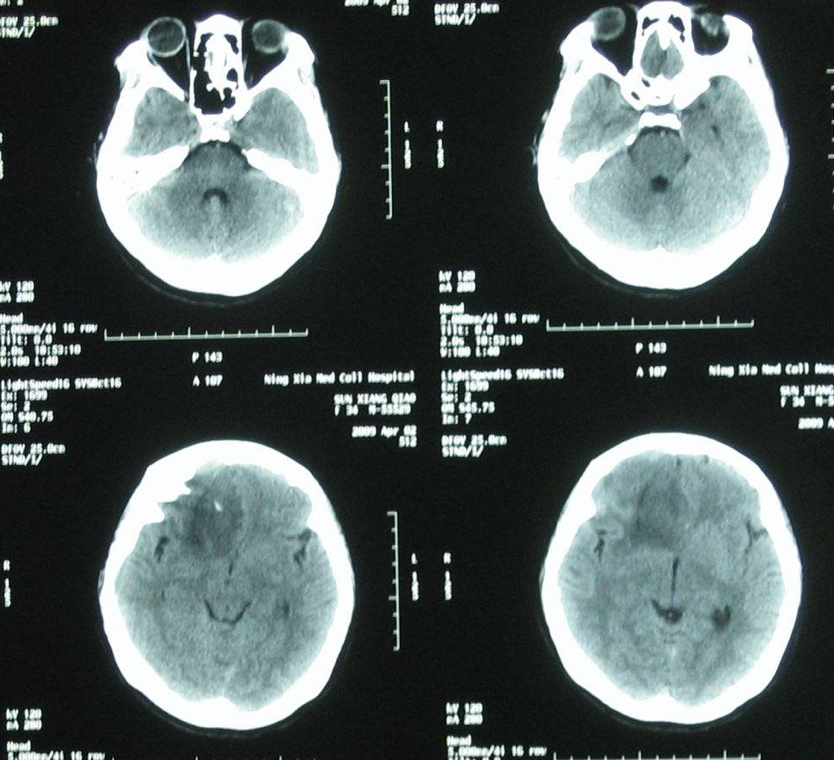

颅内肿瘤也称为脑肿瘤,它是神经系统中常见的疾病之一,对人类神经系统的功能有很大的危害。一般分为原发和继发两大类。原发性颅内肿瘤可发生于脑...

人们所说的 脑癌 通常指的是脑肿瘤,又称颅内肿瘤,它是指生长在颅腔的新生物,可起源于脑、脑膜、神经、血管及脑附件,或由身体的其他组织或脏器...